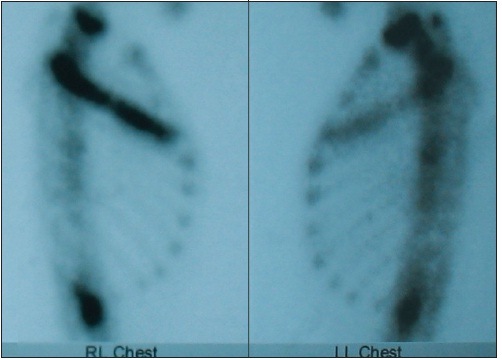

A bone scan obtained 6 months later demonstrated increased uptake on delayed images in the right third rib (Figure 2), the greater trochanter of the left femur, and the right first metatarsal. Biopsy specimens of the third rib revealed osteoblastic rimming of the bony trabeculae and paratrabecular fibrosis with scattered collections of plasma cells and lymphoid cells; there was no evidence of malignancy. The results of CD1a and S100 staining were normal, ruling out Langerhans cell histiocytosis.

Figure 2 – A technitium99 bone scan obtained for this patient shows increased radiotracer

uptake diffusely in the right third rib on delayed images.